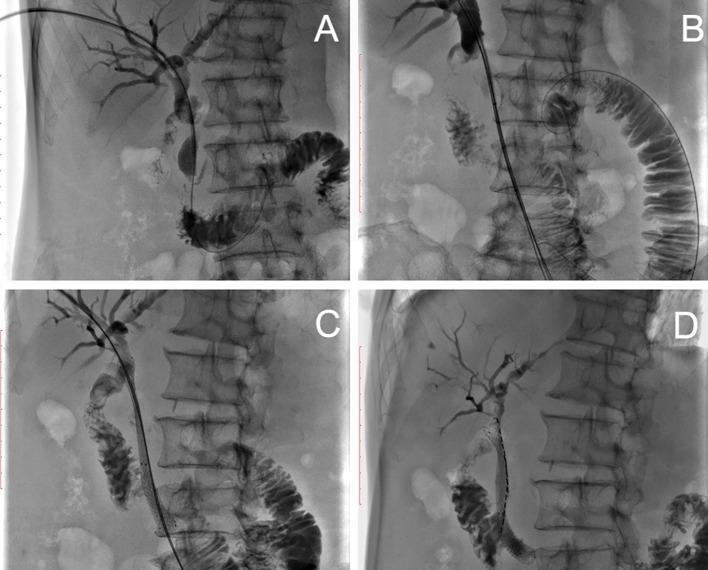

From 2016 to 2018, 68 patients diagnosed with malignant obstruction in the porta hepatis were retrospectively included in this study. Twenty-eight patients (group A) received stent placement with iodine-125 seed-strand implantation, and 40 patients (group B) received stent placement only. All patients underwent numerous transarterial chemoembolizations (TACE) after stent implantation. All patients were followed up until death. Clinical data, stent patency and survival time were recorded for further analysis.

There was no significant difference between the two groups in terms of length of malignant obstruction and baseline characteristics. 68 stents were successfully implanted in both groups.Iodine-125 seed strands were successfully deployed and completely covered the length of the stent in group A. Liver function and jaundice improved continuously in the first 9 months after treatment (P<0.05). Compared to group B, the mean stent patency time was significantly longer in group A (5.5 ± 2.09 months versus 6.86 ± 1.82 months, P<0.001). The mean survival time is longer in group A than in patients in group B (10.03 ± 3.04 months VS 7 ± 2.44 months, P<0.001).

ILBT in combination with stent implantation and TACE has proven to be a feasible and effective palliative treatment to maintain stent patency in patients with PVTT and MOJ.